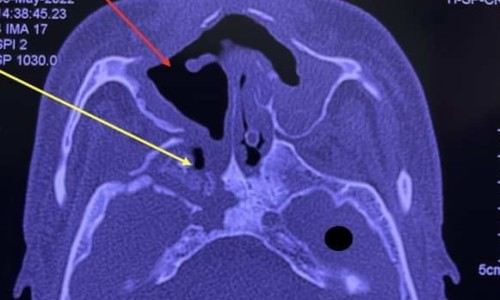

Thêm nhiều người hoại tử xương hàm sau mắc Covid

코로나19 감염 후 턱뼈 괴사된 많은 사람 추가

(TP HCM) Bệnh viện Răng hàm mặt Trung ương TP HCM tiếp nhận 16 bệnh nhân, Bệnh viện Tai Mũi Họng điều trị 5 người hoại tử xương hàm, kể từ đầu năm đến nay.

(호치민 시) 호치민시 중앙 구강외과 병원은 연초부터 현재까지 16명의 턱뼈 괴사 환자를 받았고 이비인후과 병원은 5명을 치료했습니다.

7월13일 호치민시 중앙 구강외과 병원 구강수술과장 응우옌 반 뚼(Nguyễn Văn Tuấn) 의사는 턱뼈 괴사 환자 16명 중 3건이 두개골까지 퍼졌으며 관련 많은 전문 학과가 있는 처레이(Chợ Rẫy) 병원으로 이송하여 수술했다고 밝혔습니다.

나머지 13건은 괴사된 부분 제거 수술을 한 후 최소 3주간 항생제를 썼습니다. 6개월 관찰 후 상태가 안정되고 재발하지 않으면 환자는 턱뼈 재건할 것으로 예상됩니다. 뚼 의사는 "현재 환자들은 다 안정적이고 재발 징후는 아직 없습니다."라고 말했습니다.

뚼 의사에 따르면 턱의 괴사는 위턱뼈보다 영양 공급 혈관이 적기에 발생합니다. 이런 사례는 일반적으로 당뇨 환자와 관련있는데, 뼈에 영양을 공급하는 혈관에 영향을 주거나 면역을 감소시키고 박테리아와 곰팡이 공격에 취약하게 만들기 때문입니다.

처레이 병원에서는 이들 환자의 골괴사 원인을 아직 규명하지 못했지만, 코로나19에 감염되었으며, 이비인후과 질환이나 턱관절 질환 병력이 없다는 공통점이 있습니다.

호치민시 보건부 땅 치 트엉(Tăng Chí Thượng) 국장은 이를 '새로운 문제'라 말하며 병원에 사례를 조사하고 통합할 것을 요청했습니다.

의사들은 현재까지 최근 골괴사의 증가가 코로나19와 관련 있는지 확정할 수는 없다고 합니다.

2021년 5월부터 올해 5월까지 주로 인도, 중국, 많은 아시아 국가와 일부 유럽과 미국에서 두개골 및 안면 뼈의 골괴사 환자에 대한 약 80건의 보고가 기록되어 있습니다. 델타 변이 발생 시 당뇨 환자 대부분이 코로나19에 감염되었습니다.